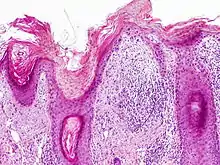

Histopathology

On histologic examination, actinic keratoses usually show a collection of atypical keratinocytes with hyperpigmented or pleomorphic nuclei, extending to the basal layer of the epidermis. A "flag sign" is often described, referring to alternating areas of orthokeratosis and parakeratosis. Epidermal thickening and surrounding areas of sun-damaged skin are often seen.[38] The normal ordered maturation of the keratinocytes is disordered to varying degrees: there may be widening of the intracellular spaces, cytologic atypia such as abnormally large nuclei, and a mild chronic inflammatory infiltrate.[39]

Specific findings depend on the clinical variant and particular lesion characteristics. The seven major histopathologic variants are all characterized by atypical keratinocytic proliferation beginning in the basal layer and confined to the epidermis; they include:[38]